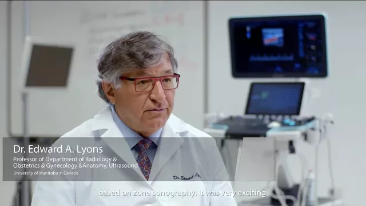

Sinds de oprichting van het bedrijf is Mindray voortdurend op zoek naar nieuwe manieren om het diagnostisch vertrouwen te vergroten. Resona 7 wordt aangestuurd door de meest revolutionaire ZONE Sonography?-technologie. Zijn nieuwe ZST+-tilt de kwaliteit van ultrasoundbeeldvorming naar een hoger niveau door middel van zoneacquisitie en kanaalgegevensverwerking.

Naast de hoogwaardige beeldvormingskwaliteit verbetert de Resona 7 tevens de klinische onderzoeksmogelijkheden met de revolutionaire V Flow voor vasculaire hemodynamische evaluatie, en de intelligentste vlakacquisitie van een 3D-gegevenssets voor de diagnose van het foetale, centrale zenuwstelsel. Met zijn combinatie van de meest intu?tieve, op vingerbewegingen gebaseerde multi-aanrakingsbediening en alle essenti?le klinische functies loopt de Resona 7 voorop in de nieuwe golven van ultrasoundinnovatie.